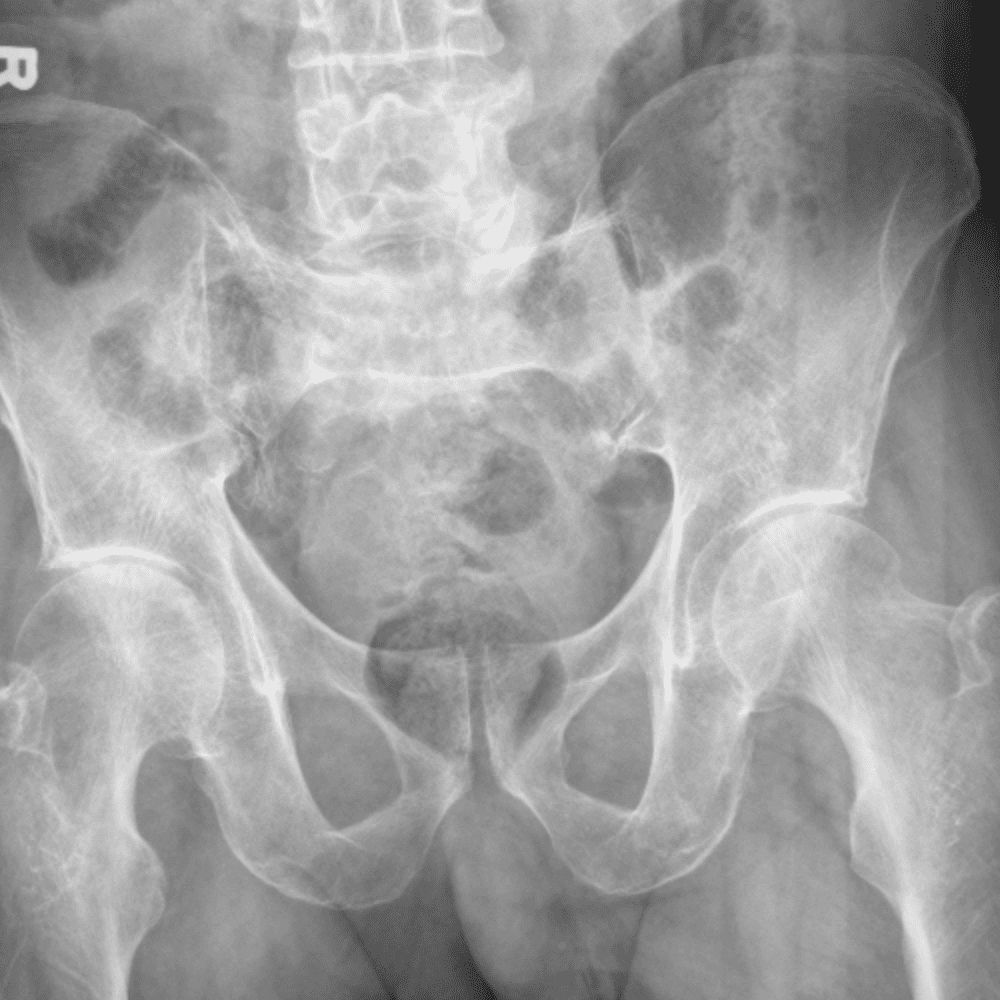

通过包含微妙或困难的病例和一些正常病例来模拟值班。

30 病例